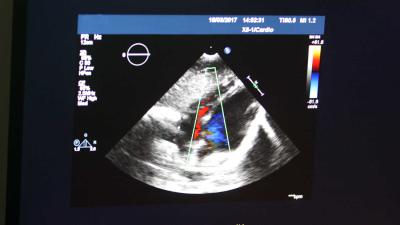

Minister Bruno Bruins van Medische Zorg laat een nieuwe behandeling bij chronisch hartfalen voorwaardelijk toe tot het basispakket van de zorgverzekering. 'De